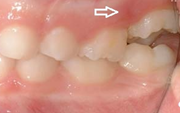

Esimeste molaaride (purihammaste) lõikumine. 1. molaaride ektoopilise lõikumise jälgimine. Ülemised ja alumised esimesed purihambad e. molaarid lõikuvad orienteeruvalt6-7-aastaselt piimahammaste rea lõppu. Enamasti lõikuvad samanimelised jäävhambad paaridena. Normaalne lõikumise Loe edasi »

- valehambumus (18)